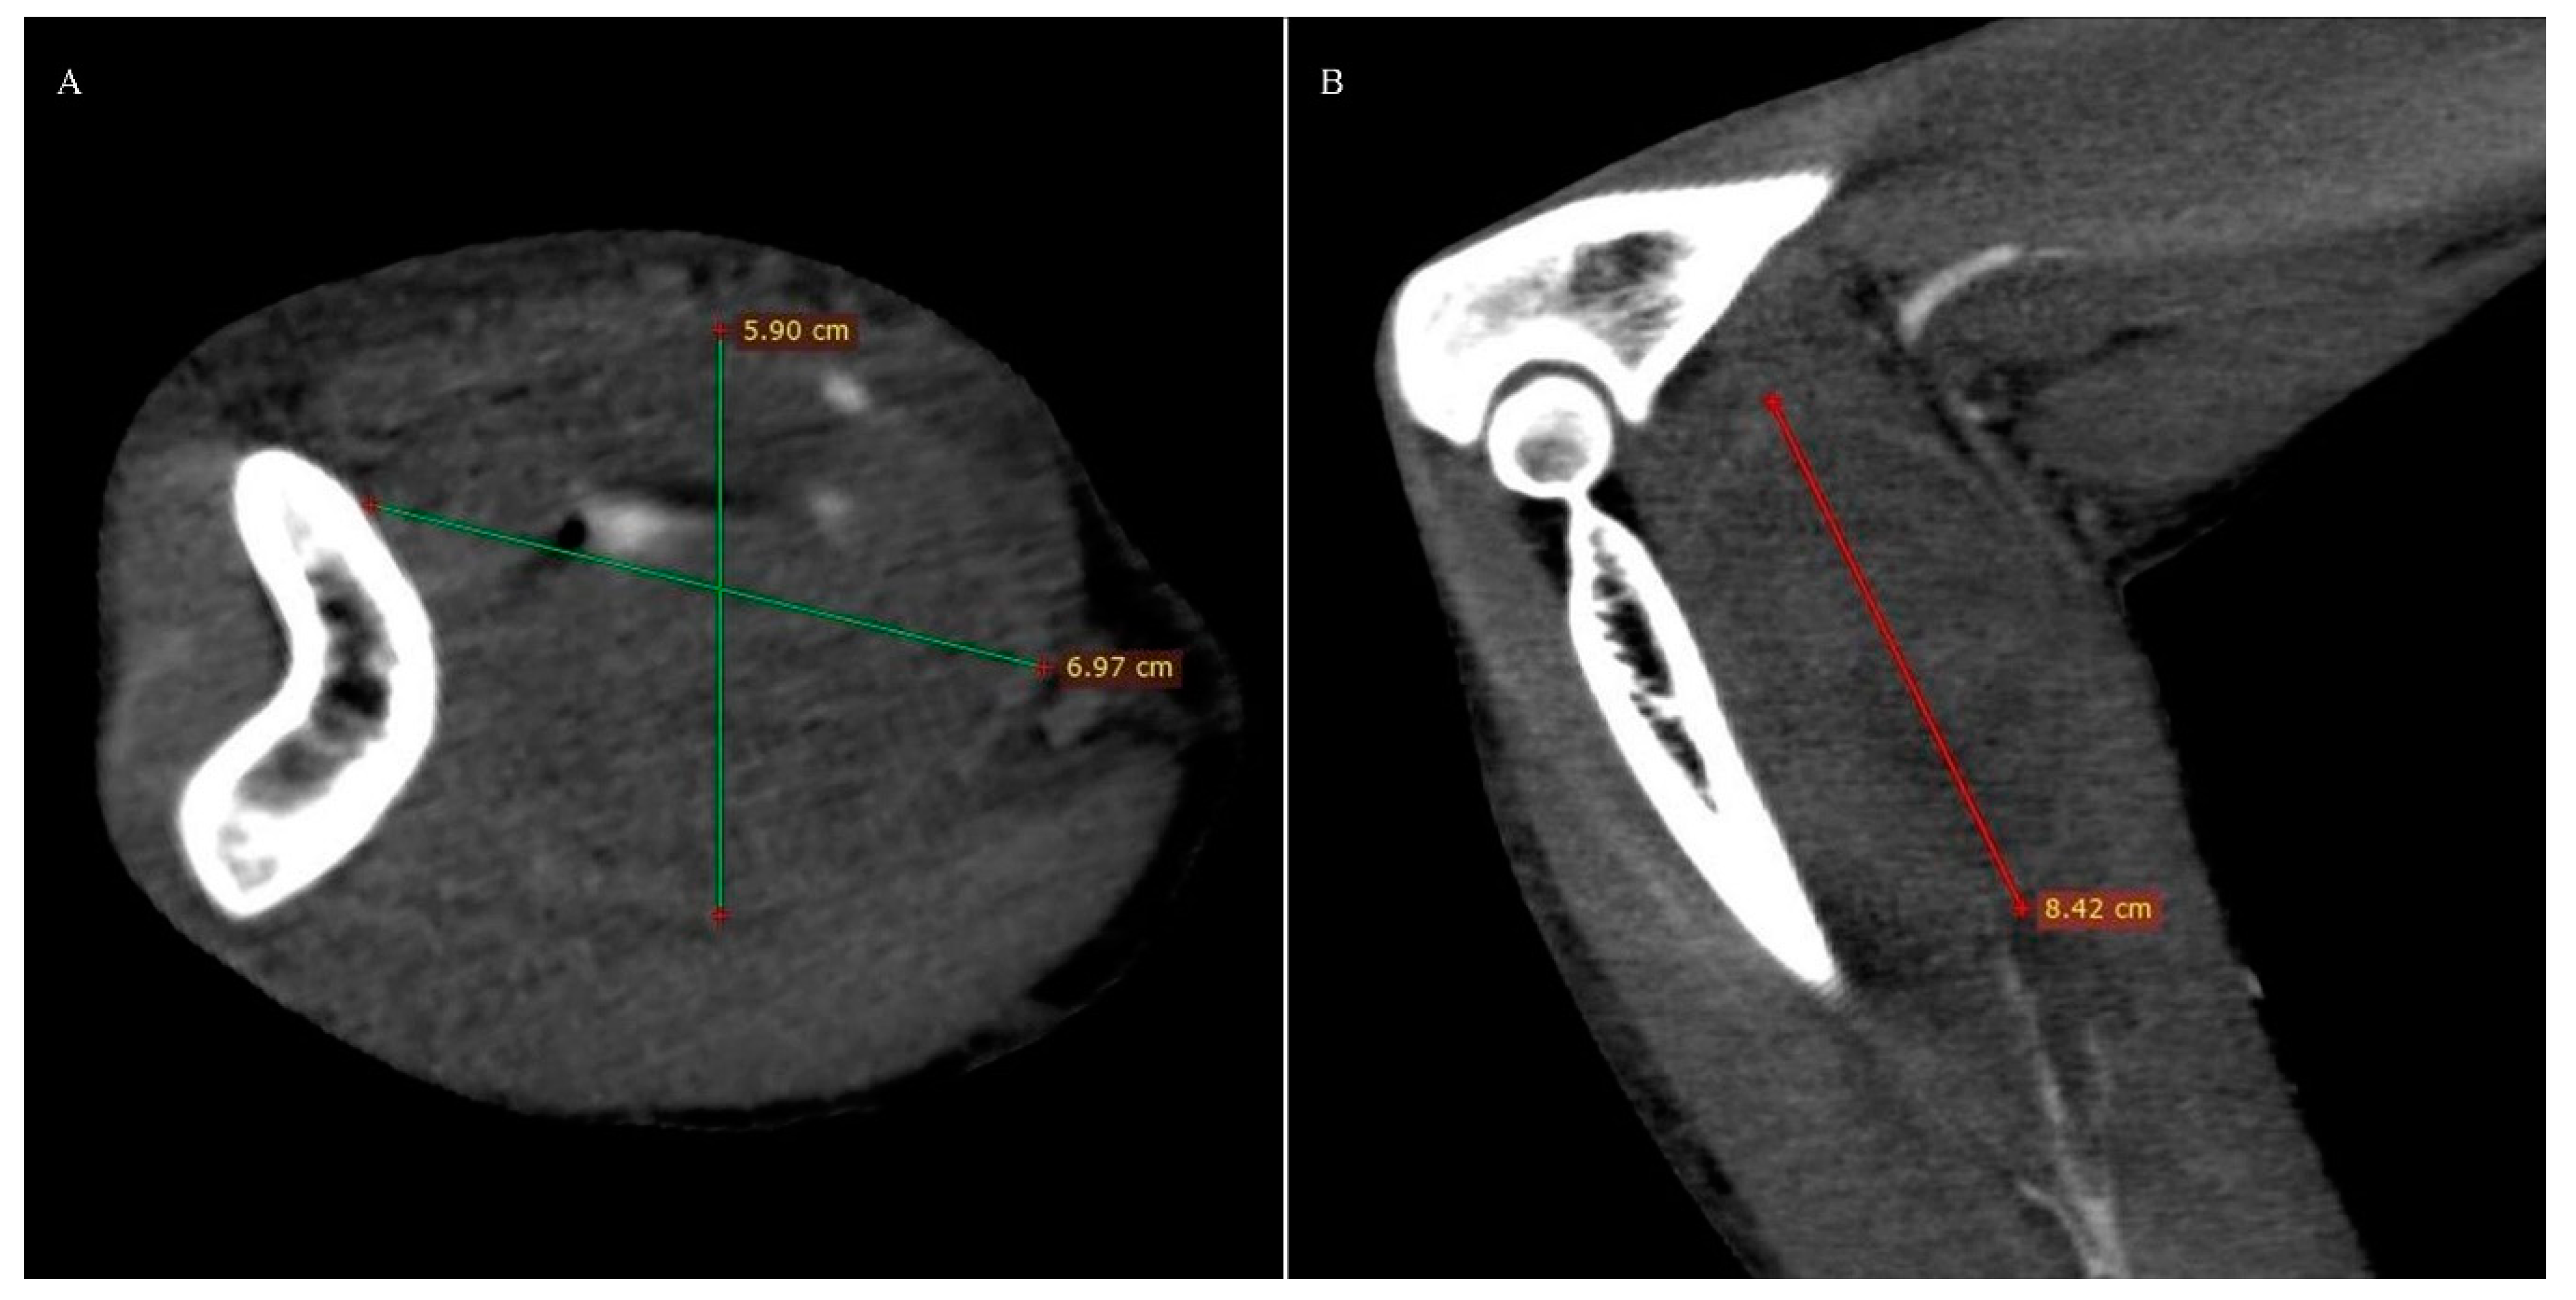

Computed tomography angiography (CTA) of the right upper limb was performed in 5.0- and 0.5-mm layers. The examination showed a non-dilated aortic arch with an independent left vertebral artery ostium between the ostia of the left common carotid artery and the left subclavian artery (Figure 1). Moreover, non-dilated arterial vessels of the right upper limb were visualized—the brachiocephalic trunk, the right subclavian artery, the right axillary artery, the right brachial artery, and the arteries of the right forearm. At the level of the distal epiphysis of the right humerus, just before the division of the brachial artery into the arteries of the forearm, a leakage of the contrast agent beyond the lumen was found, consistent with active bleeding from the injured brachial artery (Figure 2). At this level, a layered soft tissue hematoma was visualized around the brachial artery with approximate dimensions of up to 7.0 cm × 5.9 cm in cross-section and 8.4 cm in the longitudinal dimension (Figure 3). Within the soft tissue hematoma, a high-density, metallic foreign body up to about 0.7 cm in cross-sectional dimensions was localized (Figure 4).

Figure 3. Right upper limb computed tomography angiography. MPR reconstruction. Soft tissue hematoma around the brachial artery: (A). Axial view. (B). Coronal view.